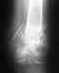

Здравствуйте. После фиксации перелома проксимального отдела бедра системой Gamma у мужа появились сильные тупые боли.

Вес ~ 100кг, рост 186 см, возраст 35 лет. Боли после операции появились сразу, не проходят. Болит иногда в месте перелома, иногда ниже, отдает до середины голени по передней поверхности ноги. Купируется нимесилом, ортофеном. Подскажите пожалуйста, с чем это может быть связано.

Чтобы сколько-нибудь предметно оценить ситуацию, нужно увидеть рентгенограммы. Хотя бы на сегодня. Еще лучше их сопоставить со сделанными непосредственно после операции.